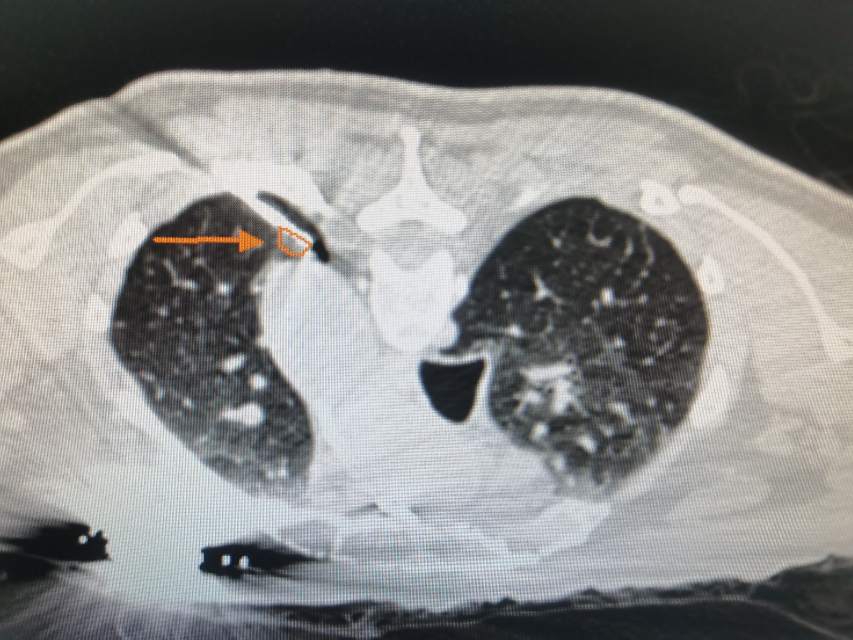

打开片子一看,李医生不由眉头一皱,这个结节生的位置真是非常的奇特,贴近胸膜还十分靠近主动脉。胸膜是肺表面的一层生物结构膜,轻易不能损伤,否则会有气胸等等问题。主动脉就更不得了了,碰也不能碰,一旦破裂真的是十分凶险,危及生命!

手术前李医生对肺结节进行了一个三维重建,明确了肺结节跟血管和胸膜之间的关系,然后对他的整个手术的操作路径进行了周密和详细的规划和预测,在手术的当天也把林老师的整个呼吸和血压心率控制在比较平稳的范围,并且对他的身体状态进行了合适的调整,让林老师在一个比较舒适和平静的状态接受手术,最大限度的减少其他因素对手术的影响。

正如手术前的预测,术中消融针一次到位,完美避开胸膜和主动脉直接到达结节的位置,真可谓一针扎进结节里!

而且经过深思熟虑,李医生特意给他选择了冷冻消融治疗,对血管和胸膜的刺激最少,而且可以最大范围的包裹住肺结节,对肺结节里面的病灶进行完美的杀灭。

手术后的CT也完美的验证了术前的预测,冷冻消融完美的包裹住了肺结节,同时对胸膜和肺动脉主动脉没有任何的影响,随着时间的推移,冷冻形成的病灶会逐渐吸收并消失。肺结节消融,冷冻消融,这是一次完美的手术,林老师非常满意的收获了不手术治疗肺结节带来的快乐!